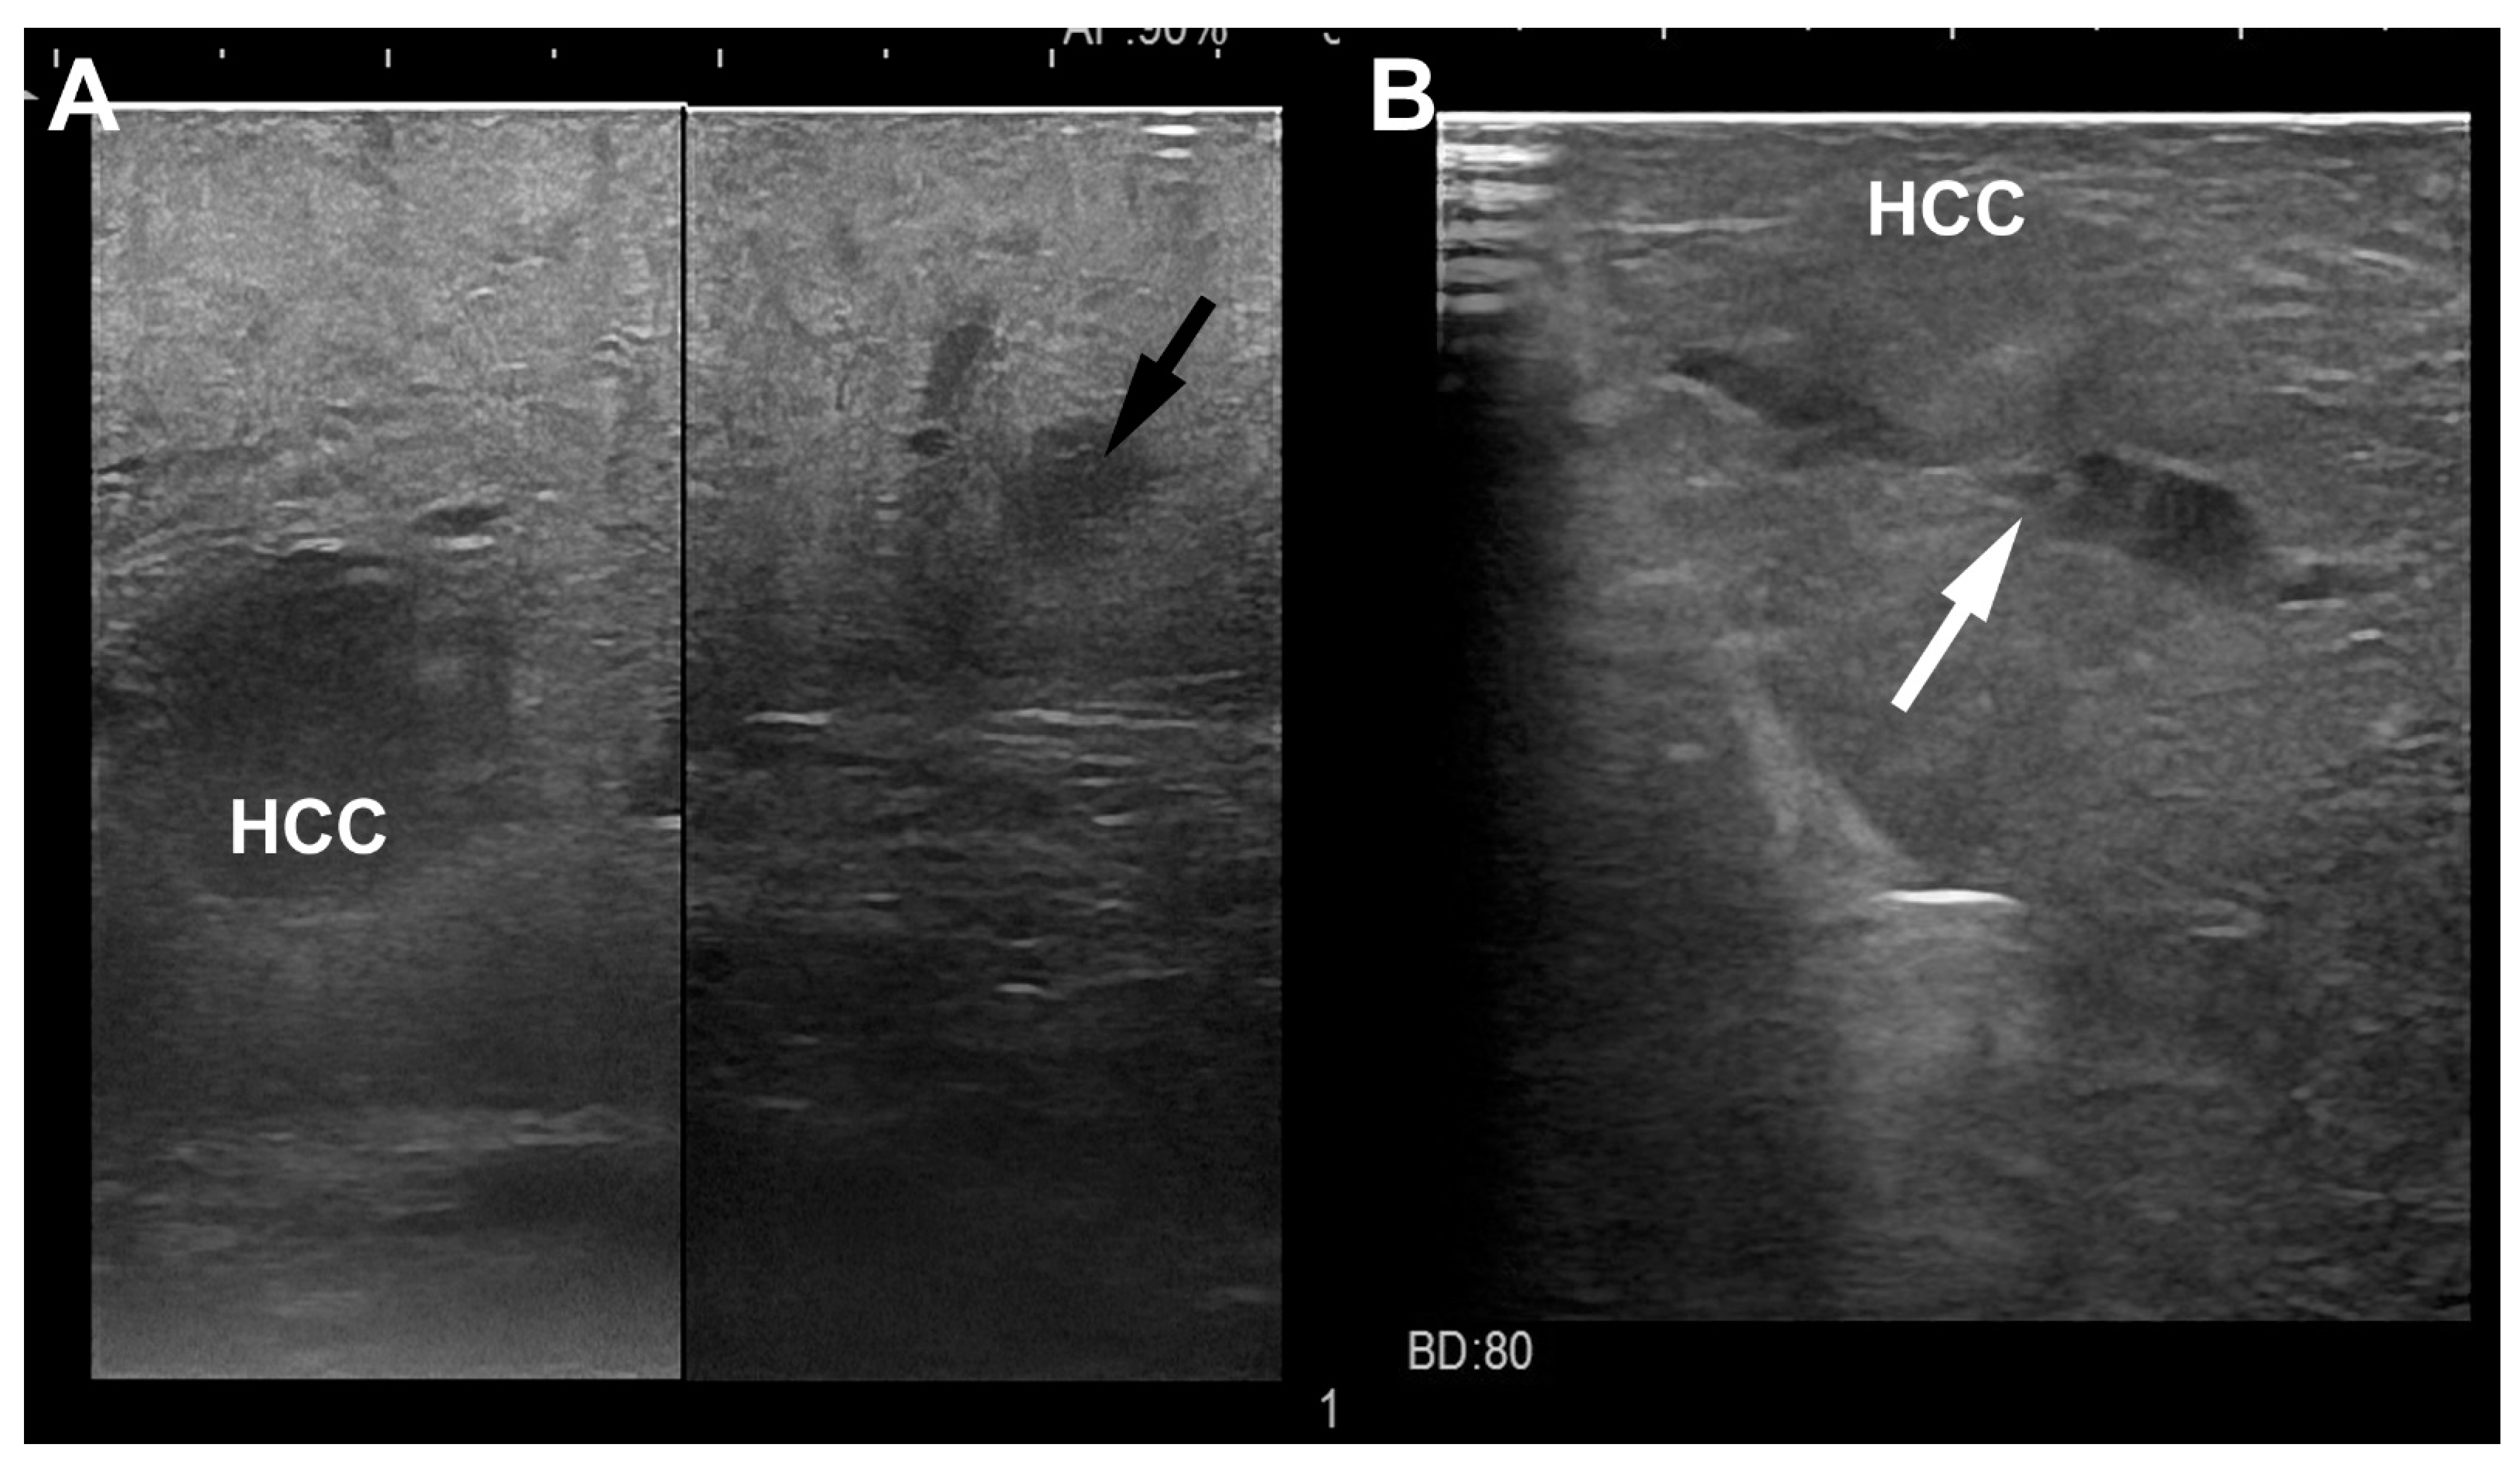

4. LUS Evaluation

- Santambrogio, R.; Cigala, C.; Barabino MMaggioni, M.; Scifo, G.; Bruno, S.; Bertolini, E.; Opocher, E.; Bulfamante, G. Intraoperative ultrasound for prediction of hepatocellular carcinoma biological behavior: Prospective comparison with pathology. Liver Int. 2018, 38, 312–320. [Google Scholar] [CrossRef]

- Santambrogio, R.; Barabino, M.; D’Alessandro, V.; Iacob, G.; Opocher, E.; Gemma, M.; Zappa, M.A. Micronvasive behaviour of single small hepatocellular carcinoma: Which treatment? Updates Surg. 2021, 73, 1359–1369. [Google Scholar] [CrossRef]